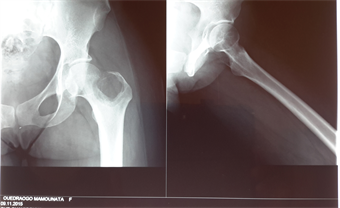

Mrs. SM, a 35-year-old patient consulted in the department for pain and dodge lameness of the left hip evolving for six months around. There was no notion of trauma. There was no specific pathological history. On examination, there was a pain awakened to the palpation supported by the greater trochanter and to the mobilization of the hip. The mobility of the joint was normal. The general condition was well preserved and the biological balance showed no abnormality. The standard X-ray of the frontal pelvis and the profile hip showed a circumscribed osteolytic image of the greater trochanter and of the femoral neck (Figure 1).

Figure 1. X-ray of the pelvis showing the tumor.